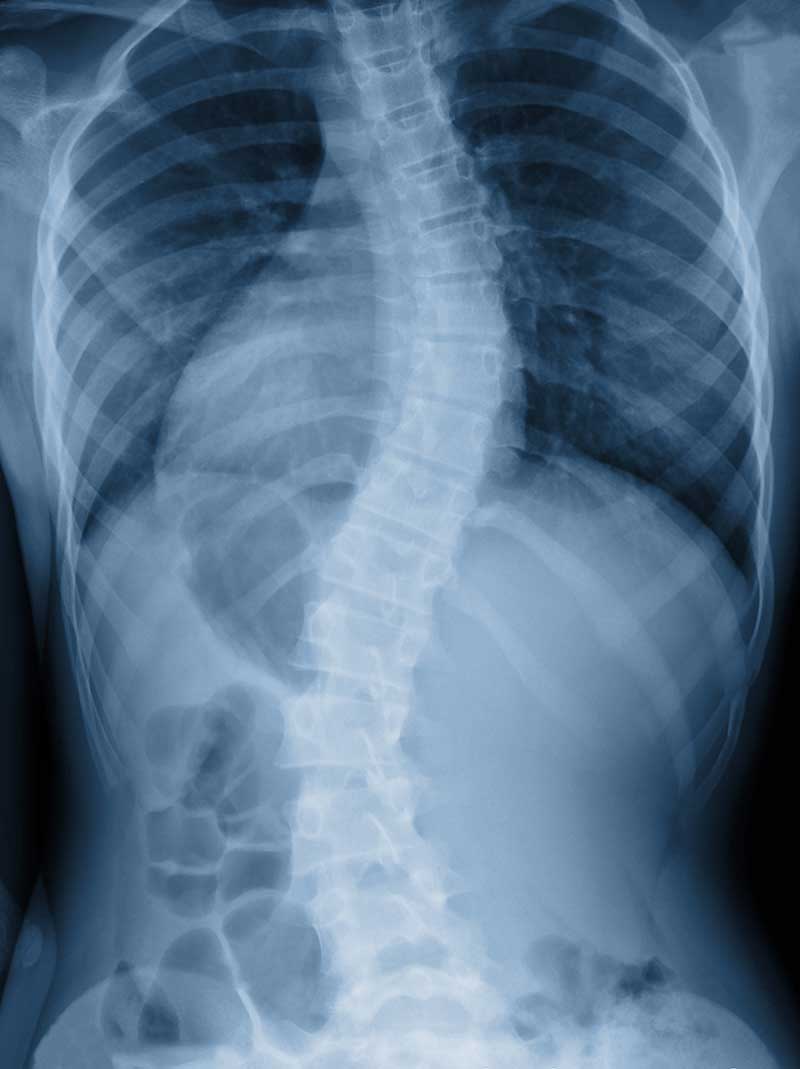

Scoliosis

When detected early, scoliosis can be managed and treated to prevent the problem from getting worse. With scoliosis, the spine has abnormal curvatures to the side or even twists. Most cases of scoliosis appear for unknown reasons as scoliosis tends to develop before puberty in adolescence, in children who previously had no spine issues.